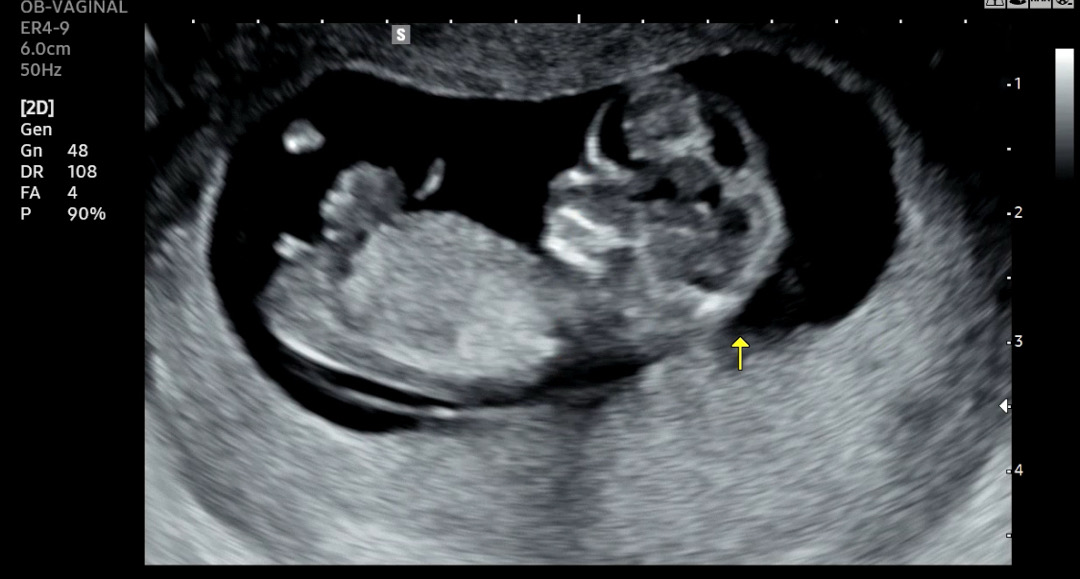

이사진으로 각도법 볼수잇을까요? 니프티를 안해서 기다리는 시간이 너무 기네요ㅠㅠ 고수님들 부탁드려요>_<